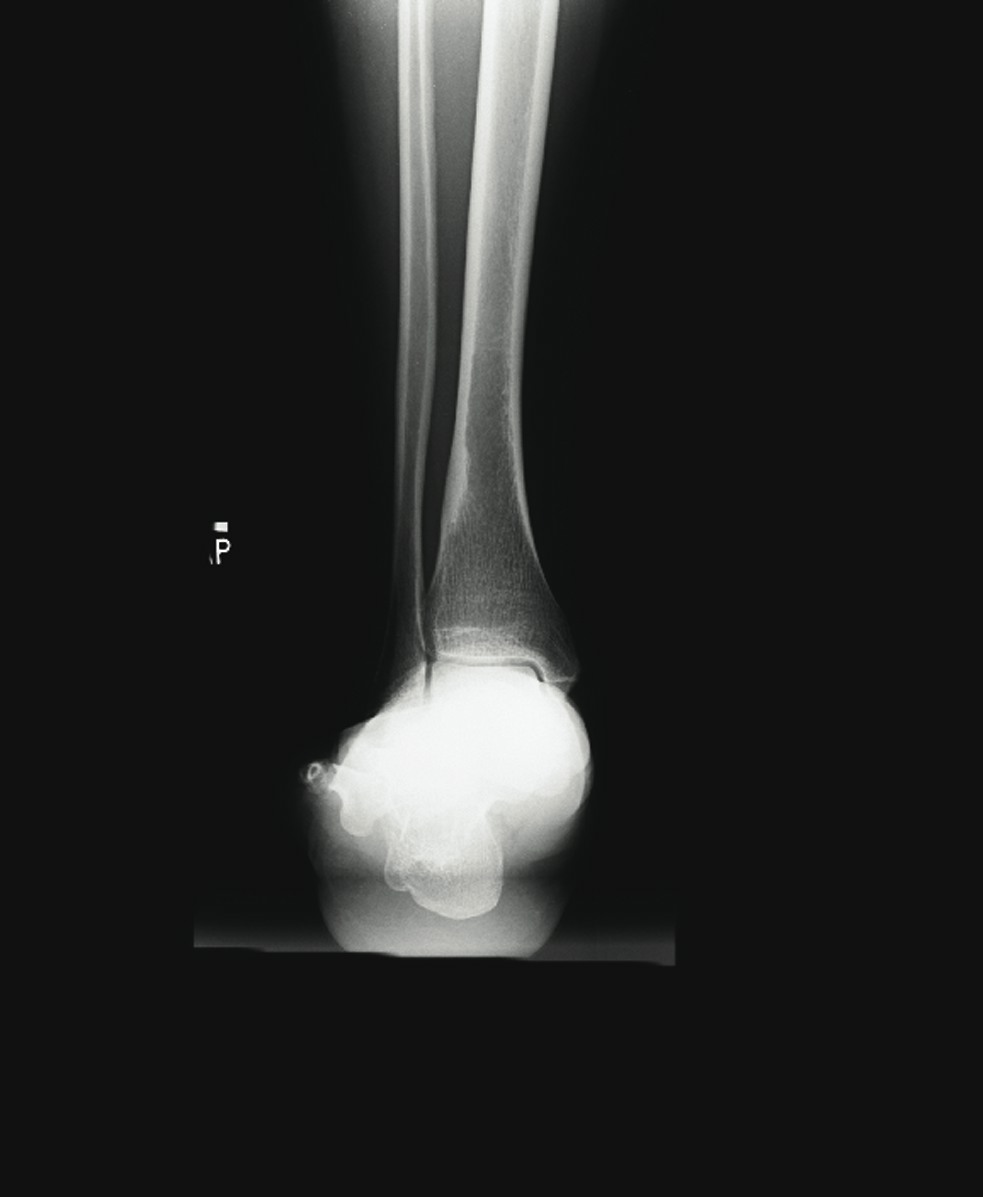

Adult-acquired flatfoot (AAF) is one of the more common conditions that podiatrists see in practice. With this in mind, some of the leading experts on this subject shared their views and experience on this subject. They discuss the role of diagnostic imaging, their use of conservative treatments and their perspectives on appropriate surgical procedures. Without further delay, here is what they had to say. Q: What ancillary studies are required for proper diagnosis and treatment selection for the adult-acquired flatfoot? A: Michael S. Lee, DPM, says AAF is generally a clinical diagnosis. Other than the physical exam, Shannon Rush, DPM, says a proper radiographic evaluation is the most important aspect of diagnosing AAF and arriving at an appropriate course of treatment. Dr. Rush emphasizes the inclusion of foot and ankle views as well as hindfoot alignment and long leg calcaneal views. All the panelists agree that neutral position X-rays are helpful in determining the degree of the deformity and what procedure one should perform. Alan Catanzariti, DPM, says it is important to evaluate the talus-first metatarsal angle on both AP and lateral radiographs. He adds that the AP views also enable one to see the amount of talar head that is covered by the navicular. Standard radiographs also allow clinicians to assess the tritarsal complex for degenerative changes, according to Dr. Catanzariti. He says these degenerative changes may indicate an arthrodesis procedure as opposed to performing reconstructive osteotomies or soft tissue procedures. The majority of the panelists recommend obtaining ankle X-rays in order to detect valgus deformity within the ankle. When there is valgus deformity within the ankle joint, Dr. Catanzariti will typically consider performing a medial displacement osteotomy of the calcaneus. “This helps decrease the tension within the deltoid ligament and prevent further attenuation of medial soft tissue structures,” explains Dr. Catanzariti. In cases of end-stage flatfoot deformity, Jordan Grossman, DPM, says AP ankle views are useful in evaluating for deltoid ligament insufficiency and valgus deformity of the talus within the ankle mortise. Gerard V. Yu, DPM, and Dr. Catanzariti agree with Dr. Rush about the value of obtaining long leg axial films. Dr. Catanzariti says long leg axial views and Saltzman views allow one to evaluate the calcaneus, subtalar joint, ankle joint and tibia relative to one another. He adds that these views often facilitate appropriate procedure selection. Lower-extremity alignment views may also be indicated in certain instances, according to Dr. Rush. Dr. Grossman concurs, noting that obtaining Cobey and hindfoot alignment views are useful in severe cases and with lower-extremity deformity. When it comes to magnetic resonance imaging (MRI), Dr. Rush says he “rarely, if ever” uses it in his workup for AAF. Dr. Catanzariti agrees. However, if he is contemplating arthrodesis versus reconstruction, Dr. Catanzariti will sometimes obtain a MRI in order to detect early degenerative changes within the subtalar joint that are subtle on standard X-rays. Dr. Grossman concurs, noting that MRI is indicated in “select circumstances” in which the diagnosis is unclear. Dr. Lee says one may employ MRI or ultrasound imaging to evaluate the posterior tibial tendon for attenuation or complete rupture. Dr. Yu emphasizes that MRI is most helpful when clinicians use a facility that has an experienced musculoskeletal radiologist, who is knowledgeable about the clinical entity and its primary and secondary manifestations. “I believe the MRI should be part of the standard workup for AAF if you plan to do direct surgical repair alone or as part of the correction of the deformity,” maintains Dr. Yu. Dr. Lee adds that a CT scan may have limited use in determining the degree of arthrosis in stage 3 or stage 4 deformities. Gait analysis may also be helpful in procedure selection, according to Dr. Catanzariti. Q: What is the significance of the posterior tibial tendon in the adult-acquired flatfoot? A: Dr. Yu says the primary purpose of the posterior tibial tendon is decelerating internal rotation of the tibia and accordingly limiting pronation of the foot following heel strike in gait. The intrinsic pathology specific to the posterior tibial tendon is “insignificant once the deformity has occurred,” notes Dr. Rush. He says the most important overriding factor is that the tendon has functionally weakened and is unable to stabilize the midtarsal joint. Dr. Rush says this functional weakness may be due to posterior tibial tendon dysfunction (PTTD) or subluxation in the rearfoot. The posterior tibial tendon plays “a primary role in the development of AAF,” according to Dr. Grossman. Dr. Lee says the posterior tibial tendon plays an important role early in the process but its importance diminishes as the deformity progresses. He notes the spring ligament may become attenuated in some situations. While there are several possible causes of AAF, Dr. Grossman says insufficiency or rupture of the posterior tibial tendon is the most common cause. The posterior tibial tendon often may be attenuated or diseased in AAF, according to Dr. Catanzariti, but he says this can vary from patient to patient. If patients have significant symptoms as a direct result of disease within the posterior tibial tendon, Dr. Catanzariti says they may require surgical intervention, which could include a tenosynovectomy, a partial tendon debridement or actual resection of an attenuated tendon. He notes these interventions may be supported by tendon transfers. In these cases, Dr. Catanzariti prefers a flexor digitorum longus tendon transfer. Dr. Rush says the clinical view of the posterior tibial tendon or its appearance on MRI does not influence one particular reconstruction over another. When it comes to stage 3 and stage 4 AAF, Dr. Lee says the posterior tibial tendon plays little importance in function, diagnosis or surgical treatment selection. If a patient has a predisposition to excessive pronation due to a specific foot structure, Dr. Yu says the posterior tibial tendon is “very significant.” When patients have a cavus foot, he notes the inherent stability of the foot will limit pronation. However, if a patient has hypermobile joint laxity syndrome, Dr. Yu says the posterior tibial tendon will be more important as it will “work harder to prevent excessive pronation.” If one stabilizes the foot well with osseous procedures, especially fusions, the importance of the posterior tibial tendon for function decreases, according to Dr. Yu. When one performs a posterior tibial tendon transfer for other conditions (i.e., dropfoot deformity), Dr. Yu says the foot structure remains the same due to the inherent interlocking of osseous units. When performing a triple arthrodesis, Dr. Yu notes the surgeon can leave the PT tendon alone altogether unless the pain there is due to active inflammation around the tendon itself. In essence, the more inherently stable the foot is, whether by surgical fusion or anatomical stability, the less important the PT tendon is to overall foot function. Q: What conservative measures have been successful in your hands in the treatment of AAF? A: Employing orthotics in combination with antiinflammatory medications and posterior muscle group stretching provides relief in milder cases of AAF, according to Dr. Catanzariti. When it comes to stage 1 conditions, Dr. Lee notes he has had a fair amount of success utilizing figure-of-eight ankle braces along with rest, ice, NSAIDs and shoe gear modifications. He notes that stage 2 deformities have responded well to prefabricated and custom orthotics, rest, activity modification and NSAIDs. Dr. Lee has also utilized ankle foot orthoses (AFOs). Depending on the presentation and degree of the deformity, Dr. Grossman says he has had success with the aforementioned modalities as well as physical therapy, cast immobilization and a removable walking boot. Functional orthotics may be helpful in the early stage of AAF but Dr. Yu says he generally does not use them. Dr. Yu notes that some companies make a variety of orthotic devices that “are too flimsy and do not have enough substance to do the job.” Essentially, one needs to ensure bracing of the foot to the leg, according to Dr. Yu, especially in the presence of other factors like obesity, genu valgum, etc. Dr. Yu says Aircast ankle braces and similar devices may provide good relief prior to using the more sophisticated and expensive devices like the Richie Brace and AFOs. With chronic conditions, Dr. Rush will use aggressive custom orthoses, Richie Braces and the Arizona AFO prior to surgical intervention. With stage 3 and stage 4 deformities, Dr. Lee will brace them with either UCBL orthotics or AFOs. If these fail, he proceeds to surgical intervention. The other panelists concur that one can use conservative bracing for stage 3 and stage 4 deformities in patients who are not surgical candidates. In these patients, Dr. Rush has had success with the Arizona AFO while Dr. Catanzariti has utilized supramalleolar AFOs with good results. In regard to conservative therapy, Drs. Rush and Yu say there are many factors to consider including the patient’s level of activity, weight loss, patient education, proper shoe gear and rehabilitation. Realistic expectations are essential and become more important as patients progress from stages 1 to 4, according to Dr. Yu. He says a patient with stage 3 or 4 deformity and low activity may respond surprisingly well to bracing but bracing is unlikely to be successful in a highly active patient with stage 2 AAF. Q: At what point does AAF become a surgical foot? A: The majority of the panelists consider surgical treatment when the deformity is progressive, grossly unstable and doesn’t respond to functional bracing. Dr. Rush says the potential progression of the deformity is a significant concern. “Severe talonavicular and subtalar subluxation can have a devastating influence on the ankle joint,” emphasizes Dr. Rush. “If the lateral peritalar drift is left unabated, the ankle can also fall into valgus.” Dr. Lee says he performs surgery for end-stage deformities such as stage 3 and stage 4 conditions. However, Dr. Yu notes that even severe deformities do not justify surgery alone. “If the other foot is flat and asyptomatic, you may be able to manage the pathologic foot without surgery,” points out Dr. Yu. If bracing fails, one needs to turn to surgical options, according to Dr. Yu. He emphasizes that physicians should always remember to treat patients in conjunction with their disease or deformity and not the X-rays. He notes that clinical correlation is essential to effective treatment. Q: When are calcaneal osteotomies indicated in the treatment of AAF? A: Dr. Yu says these procedures are “rarely” indicated for treating AAF. He believes this approach has been abused in an attempt to avoid more time-tested techniques, such as the gold standard triple arthrodesis, especially in the later stages of AAF when the deformity can be quite severe. In his experience, Dr. Yu says the calcaneal osteotomy has little impact in resolving severe AAF “when a fusion in conjunction with tibialis posterior repair and posterior lengthening would have worked out better.” While he notes that calcaneal osteotomies are very helpful in the earlier stages of the disease, Dr. Yu emphasizes that many of these patients will do well without surgery. Drs. Grossman, Catanzariti and Lee believe calcaneal osteotomies are primarily indicated for flexible or reducible deformities. These procedures allow surgeons to correct various deformities while maintaining midtarsal and subtalar joint motion, according to Dr. Grossman. He says this will “most likely decrease the likelihood of adjacent joint demand and arthrosis that one commonly sees with an isolated or triple arthrodesis.” Citing the versatility of calcaneal osteotomies, Dr. Catanzariti calls them an excellent alternative to arthrodesis procedures. “These osteotomies spare the tritarsal complex and allow the hindfoot to function in a relatively normal fashion,” explains Dr. Catanzariti. Dr. Lee concurs. If the flatfoot is supple, he says one can achieve correction with calcaneal osteotomies while preserving most of the hindfoot motion. When it comes to late stage 1 AAF, Dr. Catanzariti will consider posterior calcaneal displacement osteotomies and sometimes uses this approach to treat early stage 2 conditions. Dr. Lee utilizes posterior calcaneal displacement osteotomies for early stage 2 AAF and employs the Evans calcaneal osteotomy and double osteotomies for late stage 2 conditions. For mid- to late stage 2 AAF, Dr. Catanzariti considers performing an anterior open wedge osteotomy in combination with a posterior displacement osteotomy. Dr. Rush says calcaneal osteotomies are a “wonderful surgical tool” for treating AAF. He performs a posterior osteotomy with any valgus malalignment of the subtalar joint when a subtalar arthrodesis is not indicated. Obtaining hindfoot alignment and long leg calcaneal axial views help in planning with this procedure, according to Dr. Rush. He maintains that clinicians must be careful to evaluate the midtarsal joint and medial column for instability and supinatus. In the presence of instability or deformity, Dr. Rush notes one must add ancillary procedures in order to stabilize the medial column. Dr. Rush adds that naviculocuneiform arthrodeses serve to stabilize the medial column and address the naviculocuneiform fault if one exists. Dr. Grossman says he typically performs calcaneal osteotomies in combination with other bony and/or soft tissue procedures. Dr. Rush does not utilize an isolated anterior calcaneal osteotomy for AAF. He says one must combine this procedure with the posterior osteotomy to correct the valgus and lateral translation in the subtalar joint. Dr. Rush strongly emphasizes paying close attention to the subtalar alignment when selecting these procedures. Dr. Lee also notes that he prefers calcaneal osteotomies over isolated hindfoot fusions when treating AAF in smokers, more active patients and those with a normal or slightly elevated body mass index (BMI). Q: When is an isolated or combined joint arthrodesis indicated in treating AAF? A: According to Dr. Yu, these procedures are indicated when there is significant deformity with significant disability and symptoms, especially in cases that involve degenerative arthritis or excessive mobility that cannot be predictably controlled by other means. When one considers performing three joint preservation procedures, Dr. Yu believes one joint fusion can achieve the same outcome. He says performing an isolated joint fusion is especially beneficial for patients who have a low level of activity and want relief of their pain and a stable foot. If one achieves the fusion in a neutral position without varus or valgus, Dr. Yu says the fusion provides “exceptional functional outcomes” with minimal stress on adjacent joints, which minimizes the risk of subsequent degenerative joint disease. “It’s all about the alignment and position of fusion,” emphasizes Dr. Yu. Over the years, Dr. Yu notes anecdotally that he has observed, examined and analyzed a large number of adult patients who had congenital coalitions, realizing they had minimal to no symptoms until their late 40s and 50s or even later. Dr. Yu says the position of the fusion is key to minimizing stress on adjacent joints and structures. Tarsal coalition patients who present early in life invariably have peroneal spastic flatfoot deformities, creating a completely different clinical problem, according to Dr. Yu. However, he emphasizes that the technique one uses to perform these fusions is important. Rigid deformities, a degenerative midtarsal or subtalar arthritis are the primary indications for using isolated or combined arthrodesis procedures, according to Dr. Grossman. He says one may also consider these procedures for obese patients with AAF or in cases of underlying inflammatory arthritis. Dr. Grossman says he typically combines an isolated arthrodesis procedure with soft tissue reconstruction and posterior muscle group lengthening. As with all arthrodesis procedures, Dr. Grossman says the position primarily predicates outcomes and patient satisfaction. Dr. Lee utilizes isolated hindfoot fusions in late stage 2 deformities when there may be mild arthrosis in one or more of the hindfoot joints, when the deformity is severe on plain radiographs or in patients with a higher BMI. A subtalar joint arthrodesis may be effective in the presence of isolated subtalar joint disease or arthritis, according to Dr. Catanzariti, but he rarely uses this procedure to treat AAF. In these cases, Dr. Catanzariti prefers a double calcaneal osteotomy for stage 2 AAF, a triple arthrodesis for stage 3 AAF and a combination of triple arthrodesis and posterior calcaneal displacement osteotomy for stage 4 AAF. On the other hand, Dr. Lee says he tends to perform an isolated subtalar joint arthrodesis in many cases of AAF but will occasionally opt for talonavicular arthrodesis in more severe cases of AAF with significant talar declination. Dr. Rush notes that painful degenerative joints and significant subluxation in the subtalar or talonavicular joints are general indications for arthrodesis. Arthrodesis of the non-essential medial column joints, such as the naviculocuneiform or metatarsocuneiform joints, can easily and effectively stabilize the medial arch, according to Dr. Rush. He adds that combining this procedure with calcaneal osteotomies can “correct most degrees of instability.” While distraction fusions are effective for lateral peritalar subluxation, Dr. Rush cautions that they often do not address the valgus or translation in the subtalar joint. According to Dr. Lee, distraction arthrodesis of the calcaneocuboid joint is a powerful procedure but does have “some elevated risk of non-union.” In the presence of supinatus or varus deformities, all the panelists agree that one must perform some type of ancillary medial column procedure, whether it is a medial column fusion or an osteotomy. Dr. Mendicino is Chief of the Division of Foot and Ankle Surgery at the Western Pennsylvania Hospital in Pittsburgh. He is a Fellow and Past President of the American College of Foot and Ankle Surgeons, and is a Clinical Professor of Surgery at the Western Campus of the Temple University School of Medicine. Dr. Catanzariti is the Director of the Residency Training Program within the Division of Foot and Ankle Surgery at the Western Pennsylvania Hospital in Pittsburgh. He is a Fellow of the American College of Foot and Ankle Surgeons. Dr. Grossman is Chief of the Section of Podiatry at Akron General Medical Center in Ohio. He is a Fellow of the American College of Foot and Ankle Surgeons, and a Diplomate of the American Board of Podiatric Surgery. Dr. Lee is a Fellow and serves on the Board of Directors of the American College of Foot and Ankle Surgeons. He is a Diplomate of the American Board of Podiatric Surgeons. He recently chaired the adult flatfoot panel and co-authored the ACFAS Clinical Practice Guidelines for Adult Flatfoot. He is in private practice at Central Iowa Orthopedics in Des Moines, Iowa. Dr. Rush is a Fellow of the American College of Foot and Ankle Surgeons. He is a Staff Surgeon within the Department of Orthopedics at Kaiser Permanente in Walnut Creek, Ca. Dr. Rush is also a Staff Surgeon with the San Francisco Bay Area Foot and Ankle Residency Program. Dr. Yu is the Director of the Podiatric Surgical Residency Program (PSR-36) and is the Chief of the Section of Podiatry of the Division of Orthopedic Surgery at the St. Vincent Charity Hospital, and at the Huron Hospital in Cleveland. He is a Fellow of the American College of Foot and Ankle Surgeons, and is a Diplomate of the American Board of Podiatric Surgery. Dr. Yu is also the Director of Program Development and a faculty member of the Podiatry Institute.